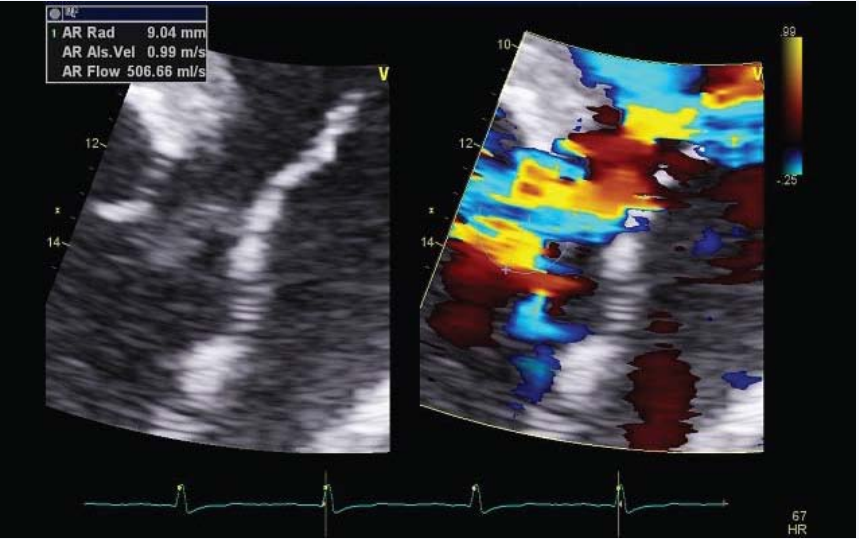

The TTE, using both multi planar and 3D acquisition (Figure 2a),

showed a severe aortic insufficiency [tricuspid valve; vena contracta = 8.3 mm, pressure half-time = 234 ms (Figure 2b),

effective regurgitant orifice area = 0.9 cm2 and regurgitant volume = 164 mL (Figure 2c)],

PISA (Proximal IsovelocitySurfaceArea) method for  aorticregurgitationquantification.

Figure 2c: PISA (Proximal IsovelocitySurfaceArea) method for aorticregurgitationquantification.